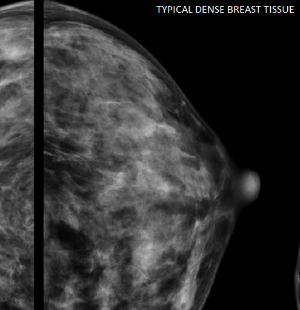

유방암은 여성의 삶에 커다란 영향을 미치는 질병입니다. 조기에 발견하면 치료 가능성이 크게 높아지기 때문에, 여성들에게 정기적인 자가 검진과 스크리닝 검사의 중요성이 강조됩니다. 유방암 2기의 경우, 종양의 크기가 2cm에서 5cm 사이이며, 림프절 전이는 있을 수도, 없을 수도 있는 단계입니다.

이는 1기에 비해 약간 진행된 상태이지만, 여전히 좋은 예후를 기대할 수 있는 단계이죠. 유방암의 조기 진단을 위해 여성들은 월경 주기를 고려하여 주기적으로 자가 유방 검진을 해야 하며, 또한 의료 기관에서 정기적인 유방 X선 촬영(Mammography)을 통해 조기 발견할 수 있도록 해야 합니다. 특히 가족력이 있는 경우, 유전적 검사(BRCA1, BRCA2 유전자 검사)를 고려하는 것이 중요합니다. 유방암 2기 진단을 받은 환자는 즉각적이고 적극적인 치료를 진행함으로써 생존율을 높일 수 있습니다. 유방암 2기는 개인의 건강 상태, 종양의 호르몬 수용체 상태, 감염의 유무 및 치료받을 수 있는 여건 등을 고려하여, 수술, 화학요법, 방사선 치료, 호르몬 치료 및 표적 치료 등의 조합된 치료 방법이 적용될 수 있습니다. 이러한 치료 방법들의 선택과 진행은 환자마다 매우 개별적인 요소에 근거하여 결정되어야 합니다.